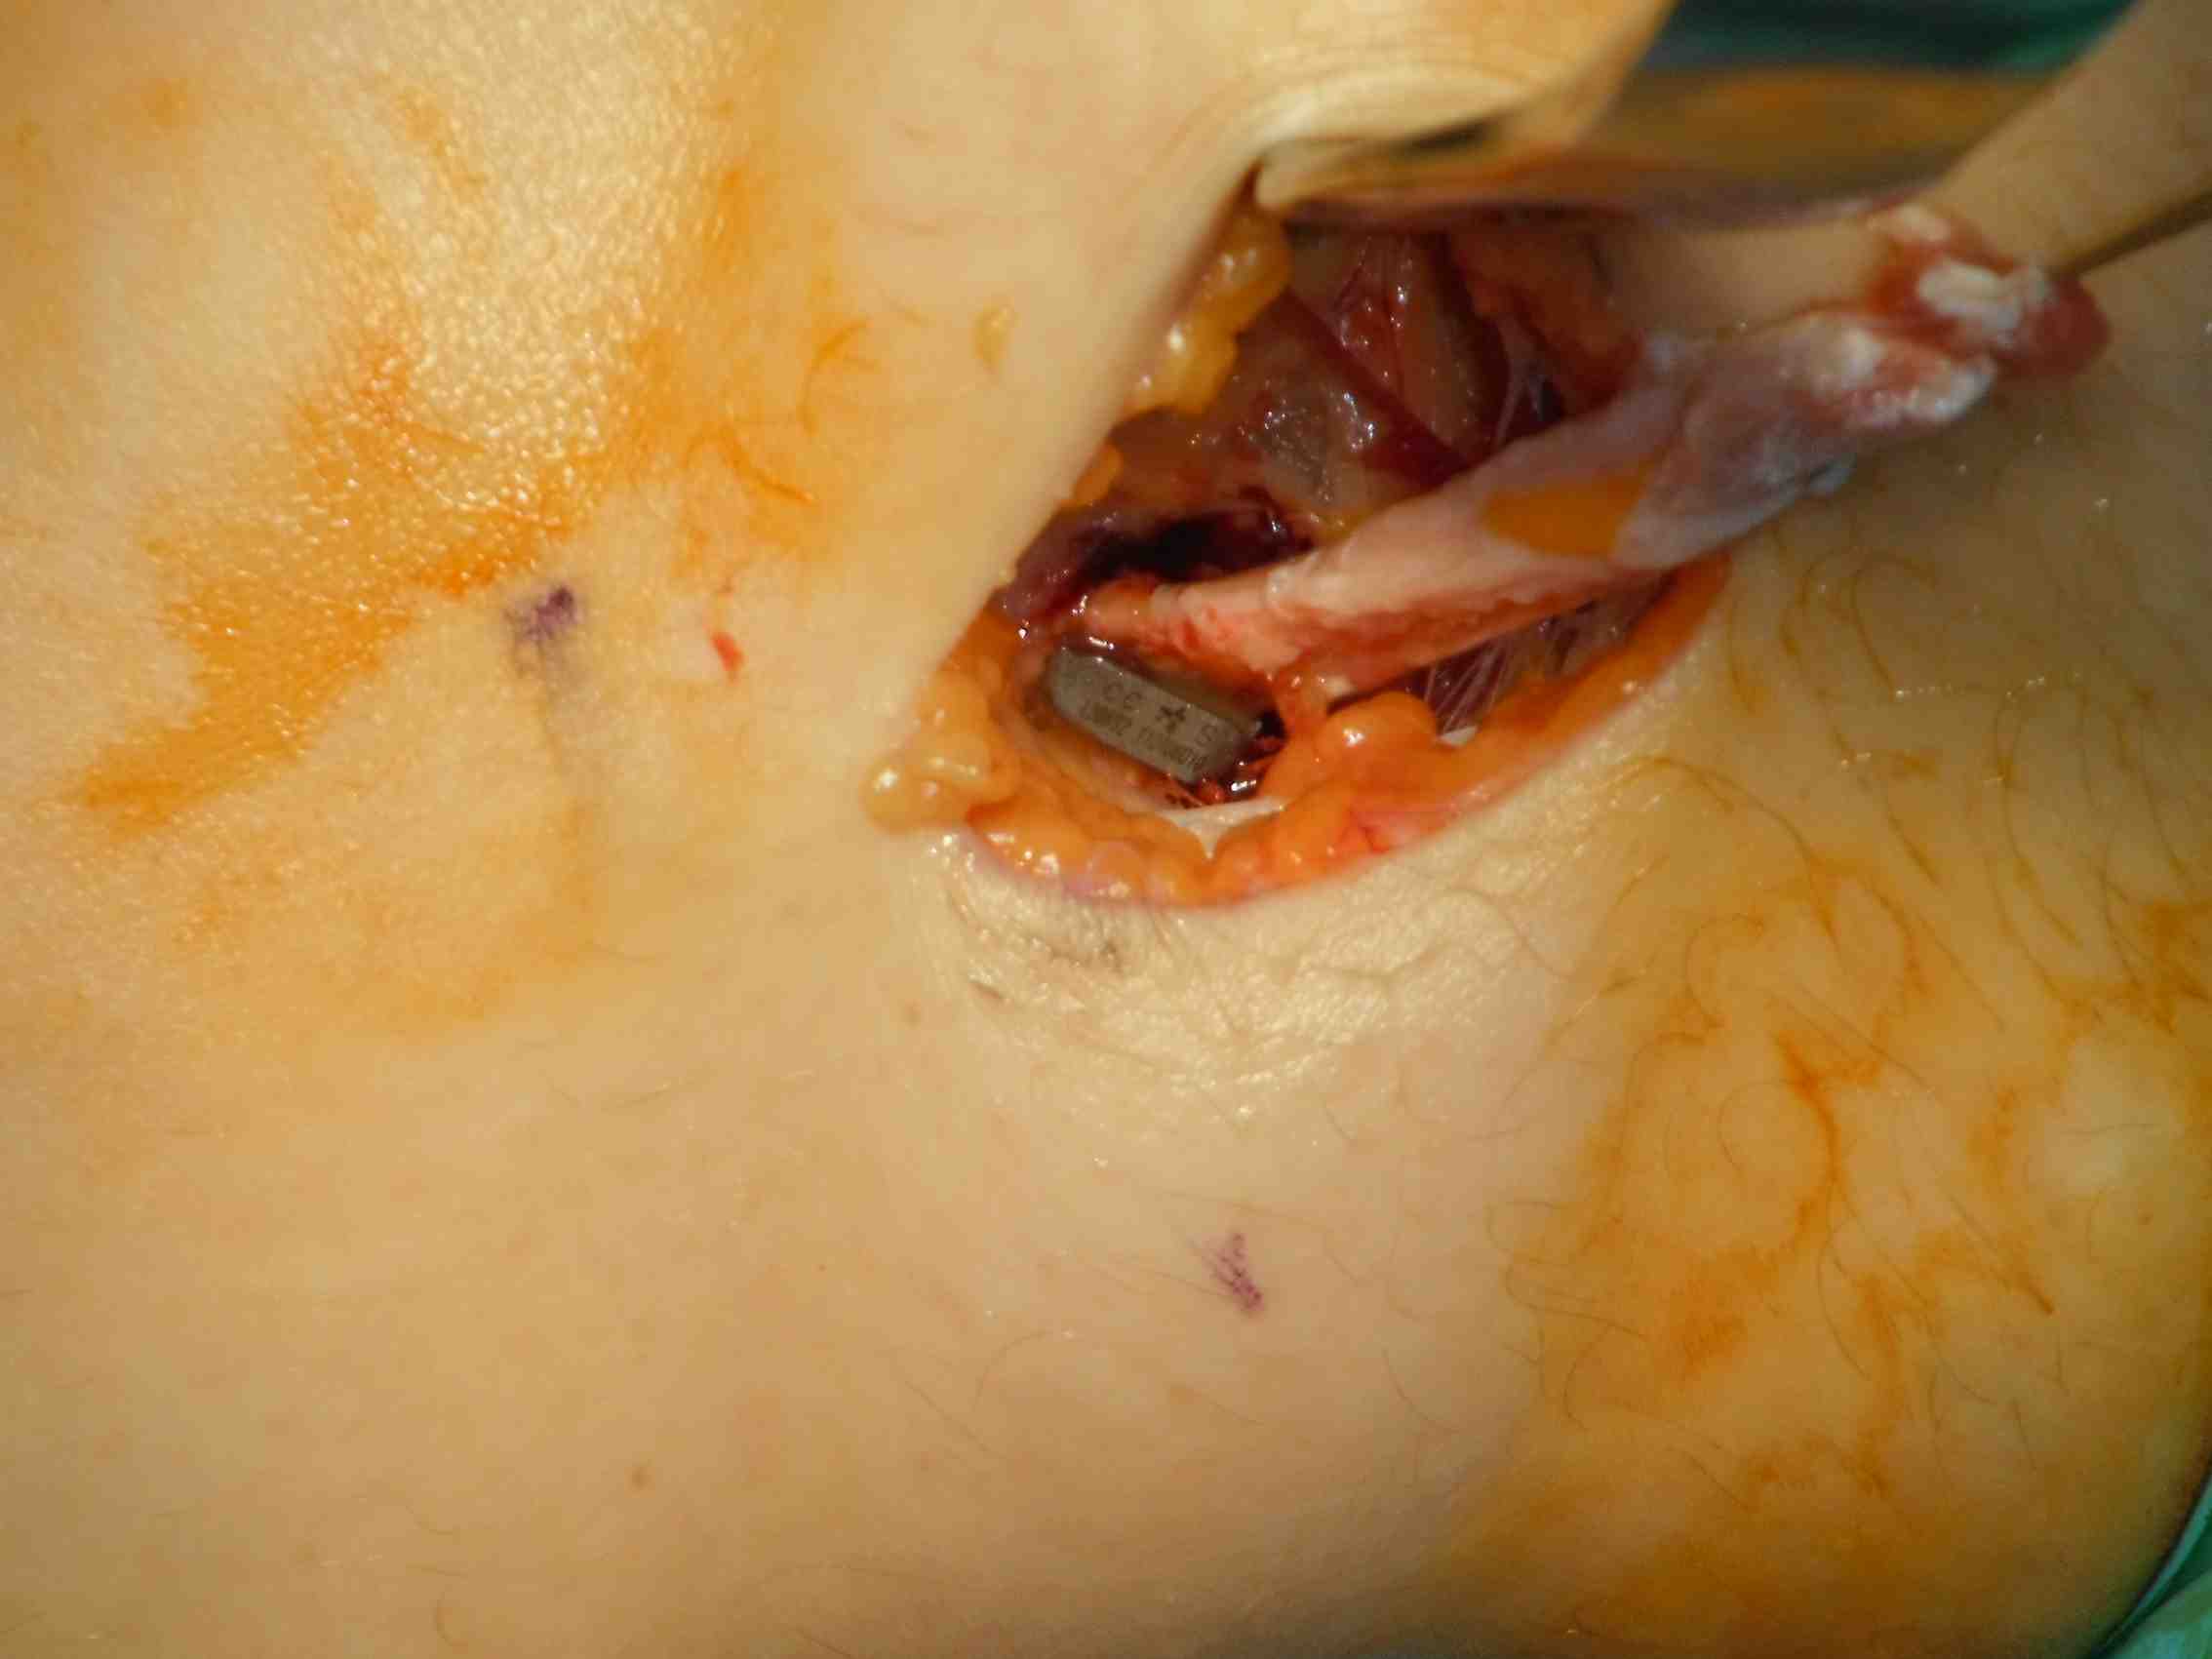

Lateral incision

- divide ITB at posterior aspect of femoral condyle

Pass curved hemostat

- from inside knee via medial arthrotomy

- pass around femoral condyle

- pass suture, retrieve graft